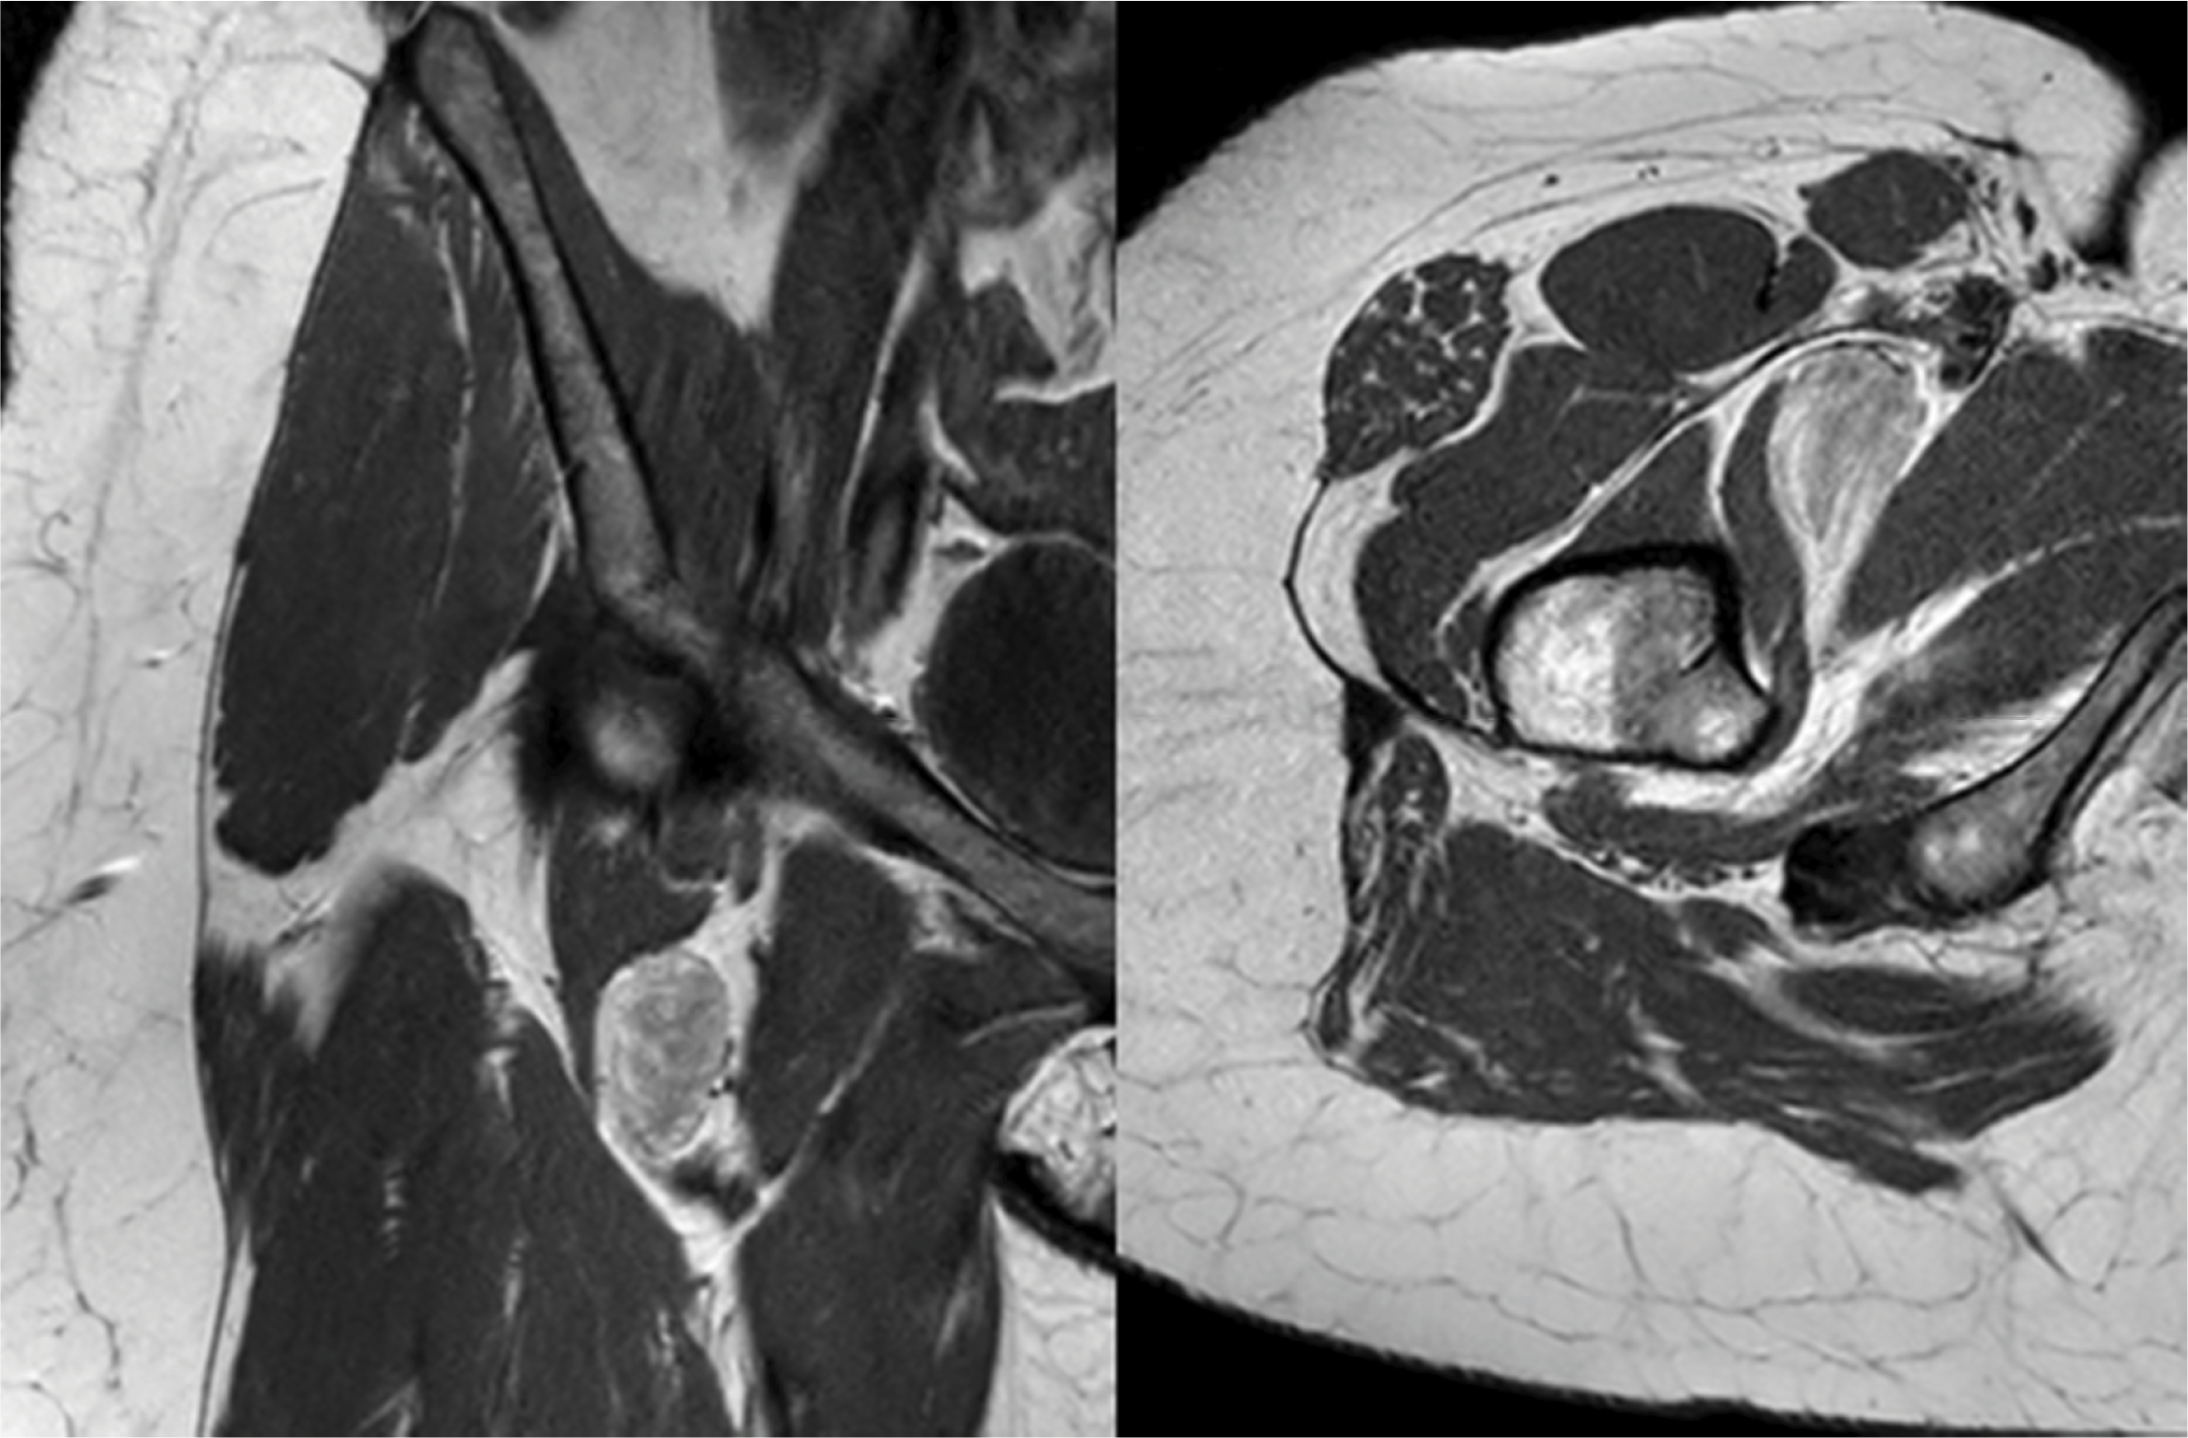

Imaging of the left hip demonstrated marked joint space narrowing due to cartilage loss and rim geodes (not shown). Magnetic resonance imaging (MRI) revealed a well‑circumscribed mass in the deep right inguinal region with mixed signal intensities on T1‑weighted imaging (Figure 1).

Figure 1

Coronal and axial T1 weighted MRI images revealed a well‑circumscribed mass in the deep right inguinal region with mixed signal intensities.